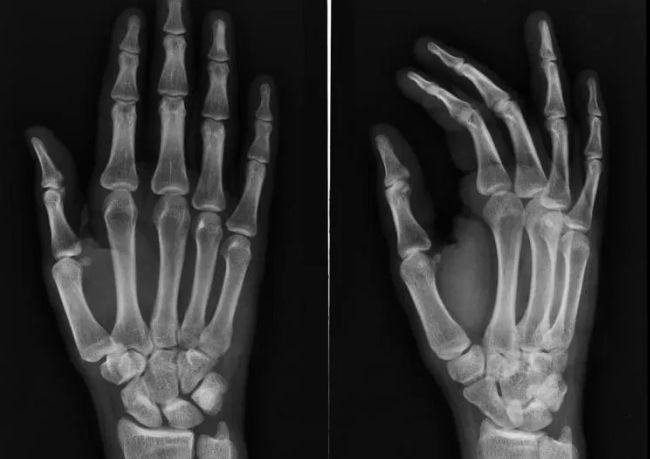

人体是由许多元素构成的,人体有许多内部器官,人体由心脏、肺、肾脏、动脉、静脉和许多其他具有各种功能的器官组成,每个器官都是人体健康和强壮所必需的。骨骼是人体最重要的器官之一,它们保持身体的平衡,保持肌肉强壮,防止我们的身体受到致命的伤害,健康的骨骼对于长寿和健康是很重要的,我们列出了很多关于人类骨骼的十大事实。

人类骨骼中最不常见的疾病之一是蜡泪样骨病,这种疾病在人类中非常罕见。在这种疾病中,一种非常坚硬的骨头会在已经存在的骨头上以不规则的方式生长,在x射线研究中,这种骨骼的生长看起来像蜡烛表面的蜡泪。